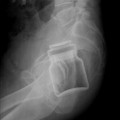

Ξένα αντικείμενα (όχι ιπτάμενα – εισερχόμενα!)

Το διαδίκτυο έχει πολλές κατασκευασμένες φωτογραφίες, αλλά αυτές που σας παρουσιάζουμε έρχονται από μια έγκυρη (και πολύ χρήσιμη) σελίδα Ακτινολογίας, το Radiopaedia.org (συν δύο μπόνους Ελληνικές φωτογραφίες!) Οι εικόνες αυτές αφορούν την («κατά λάθος» συνήθως όπως δηλώνεται) εισαγωγή αντικειμένων στο σώμα. Τις παραθέτουμε για επιστημονικούς λόγους αλλά και για να σας προειδοποιήσουμε για να προσέχετε […]